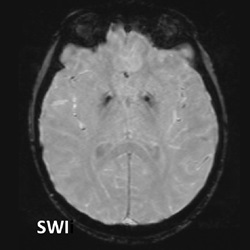

#AJNRcc >> July 22, 2024 >> What is the diagnosis for this 29-year-old pregnant woman with a 2-month history of hyperemesis gravidarum with sudden confusion, vision blurring, and altered consciousness over past 5 days? Submit your answer at https://t.co/604tEQiFye.